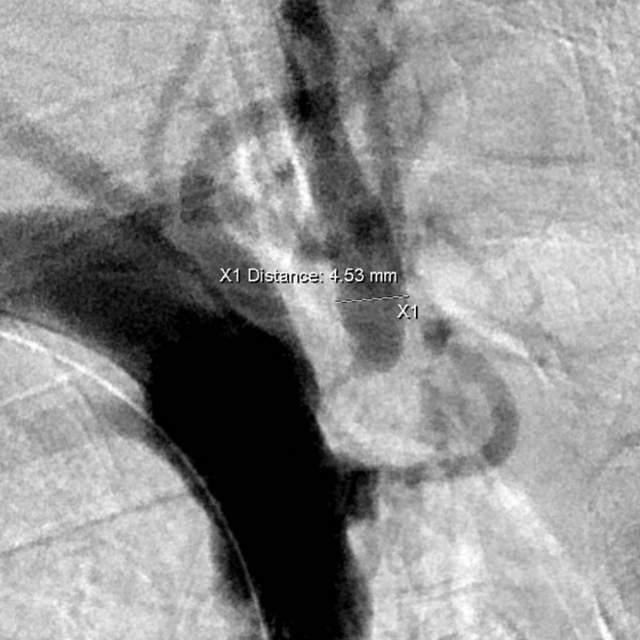

最近,儿子带老人家过来复查,检查发现右侧椎动脉起始部的狭窄越来越重,和9个月前相比,简直判若两人(管),左侧椎动脉又先天发育不好……,看来保守治疗吃药不太行,还得需要外科干预